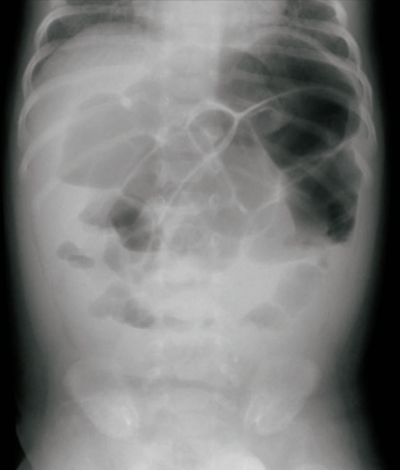

血液所見:赤血球 420万、Hb 12.3 g/dL、Ht 36%、白血球 18,000、血小板 22万。血液生化学所見:尿素窒素10mg/dL、クレアチニン0.5mg/dL、Na 135mEq/L、K 4.2 mEq/L、Cl 102 mEq/L。CRP 5.0 mg/dL。腹部エックス線写真(臥位)を別に示す。